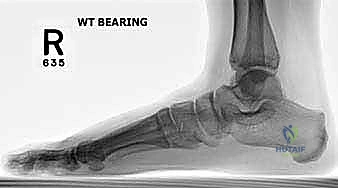

2. التصوير الشعاعي المتقدم

- الأشعة السينية مع تحمل الوزن (Weight-bearing X-rays): صور من الأمام، الجانب، والزوايا المائلة لتقييم زوايا العظام تحت تأثير وزن الجسم.

- الأشعة المقطعية (CT Scan): في الحالات المعقدة، يستخدم الدكتور هطيف الأشعة المقطعية ثلاثية الأبعاد لتقييم التئام العظام السابق، ومواقع المسامير القديمة، ودرجة خشونة المفاصل بدقة متناهية.